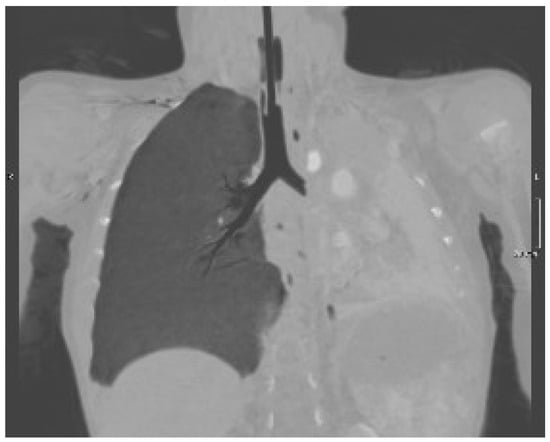

A 19-month-old boy was admitted to the Emergency Department because he fell from his baby feeding highchair. This fall occurred in apparent well-being, without the presence of anticipatory signs or symptoms. First, he fell on his gluteus and then he banged his head (occiput) on the ground. He presented with vomiting (three episodes) and he was very irritable. His respiratory rate and heart rate were >60 breaths and >150 beats per minute, while oxygen saturation was <80%. Upon physical examination, the child was hydrated and conscious, but irritable. More importantly, we noted subcostal retractions, and, at the auscultation, decreased breath sounds in the left basal part of chest. The patient was ventilated with an AMBU balloon connected to an oxygen source and monitored with a pulse oximeter. Despite our intervention, oxygen saturation fell below 70% and the more we ventilated, the more the saturation dropped down. The lung ultrasound (Figure 1) showed the absence of the typical A lines and the consolidation of the lung, which was directly visualized as a solid parenchyma. On the basis of the poor clinical condition, the patient underwent orotracheal intubation with a cuffed endotracheal tube. After the baby was stabilized, he underwent a chest computed tomography (CT) showing complete atelectasis of the left lung with an interruption of the main left bronchus at 12 cm from bronchial bifurcation (Figure 2). An FBA was suspected as the mother also stated that the baby in the previous days had an intensive cough attack and disappeared within 24 h without any treatment. Therefore, a rigid bronchoscopy was performed and an almond of 2 cm in diameter in the main left bronchus was found and promptly removed.

Regarding the radiological presentation patterns occurring in case of FBA, there is current consensus on their variety, although some features have been encountered more frequently [9]. Of the 64 children undergoing chest X-ray, Midulla et al. found localized air trapping (43.6%), atelectasis (40%), mediastinal shift (25.5%), normal radiograph (20%), visible foreign body (9.1%), and pneumonia (5.5%) [1]. However, the use of chest X-ray is controversial because many children have normal chest radiography (up to 20%), while localized air trapping and atelectasis are the most frequent radiological findings (up to 50%) [1]. Pulmonary ultrasound is highly operator-dependent but has the advantage of being X-ray free. Its role in the FBA is limited but could be useful for atelectasis detection. In fact, in the case of our baby, the lack of typical A lines and the presence of a parenchymal echogenicity allowed us in a short time to suspect the presence of a pulmonary atelectasis that could have justified the picture of incipient respiratory insufficiency. Low-dose chest CT is an effective and consistent tool for diagnosing FBA in children, with a sensitivity of 100% and specificity of 98%, so it should be used to prevent unnecessary bronchoscopies [10]. However, the radiological features lack specificity, being fundamental for the diagnosis of rigid bronchoscopy as both its diagnostic and therapeutic role.

Figure 2. Chest CT scan showing a complete atelectasis of the left lung and an interruption of the main left bronchus.